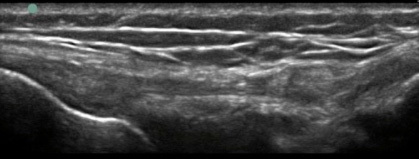

Knee Lateral Collateral Ligament Long Axis Image

LCL